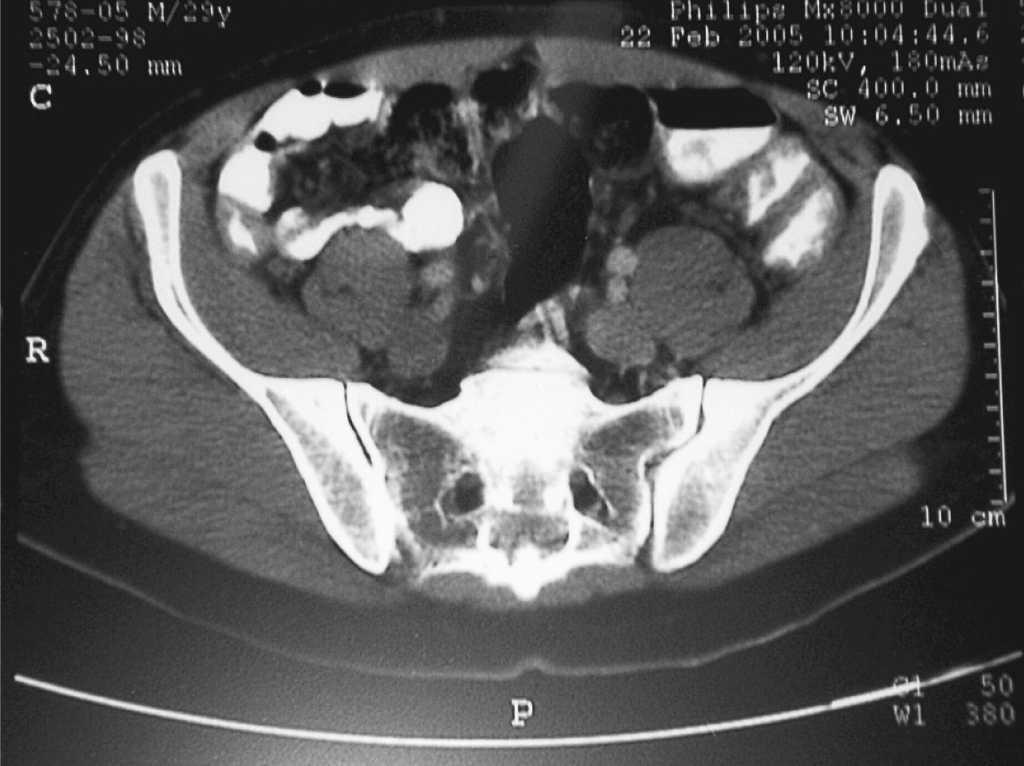

Se deriva al paciente para continuar estudio hospitalario donde se solicita nuevo estudio analítico, frotis sanguíneo, proteinograma, inmunoglobulinas, anticuerpos antinucleares, hemocultivos seriados, serología de C. burnetii, lúes, Salmonella, citomegalovirus, virus de Epstein Barr, Legionella, ecocardiograma y tomografía axial computarizada toracoabdominal. Todos los resultados analíticos fueron normales excepto el aumento de reactantes de fase aguda (VSG 95 mm/1.a hora, proteína C reactiva de 78,7 mg/l), los hemocultivos y serologías fueron negativas, el ecocardiograma dentro de la normalidad. En la tomografía axial computarizada (fig. 1) apareció un engrosamiento circunferencial de las paredes del ciego, colon ascendente, trasverso y partes del descendente, con estenosis de la luz, estos hallazgos son muy sugestivos de enfermedad inflamatoria intestinal siendo menos probables otros diagnósticos como linfoma intestinal, tuberculosis intestinal, enterocolitis infecciosas...

Figura 1. Tomografía axial computarizada toracoabdominal.